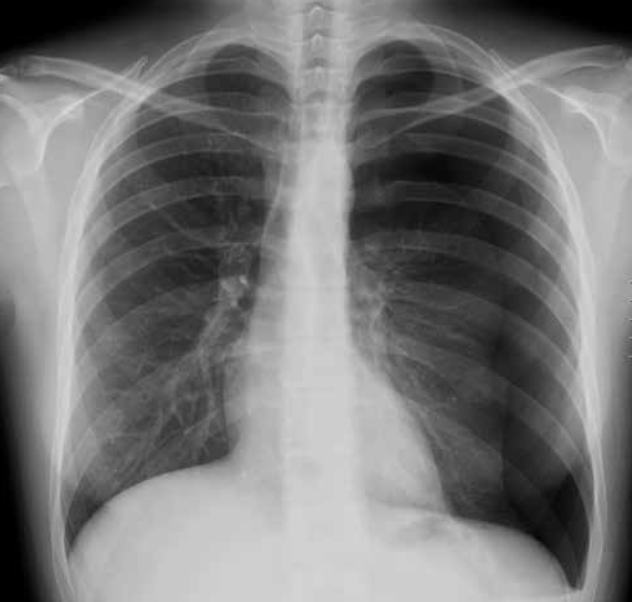

Rx normal.

Radiografía posteroanterior.

Es la proyección más utilizada. Convencionalmente se realiza en bipedestación, en inspiración profunda y a larga distancia para minimizar la magnificación.